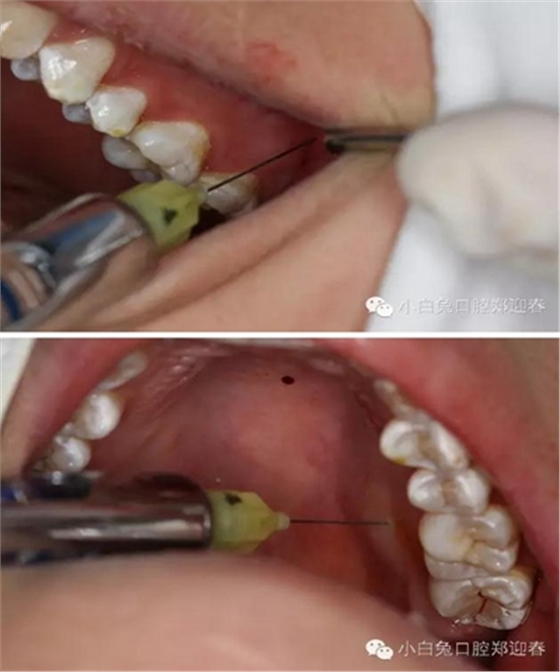

同期準(zhǔn)備拔除28,28頰側(cè)牙尖萌出,余牙面均被牙齦覆蓋。

首先,必蘭0.5ml行上牙槽神經(jīng)和腭前神經(jīng)阻滯麻醉。

采用創(chuàng)面不縫合的切瓣方式

充分暴露牙冠部分

微創(chuàng)牙挺挺出28

創(chuàng)口置入膠原蛋白明膠